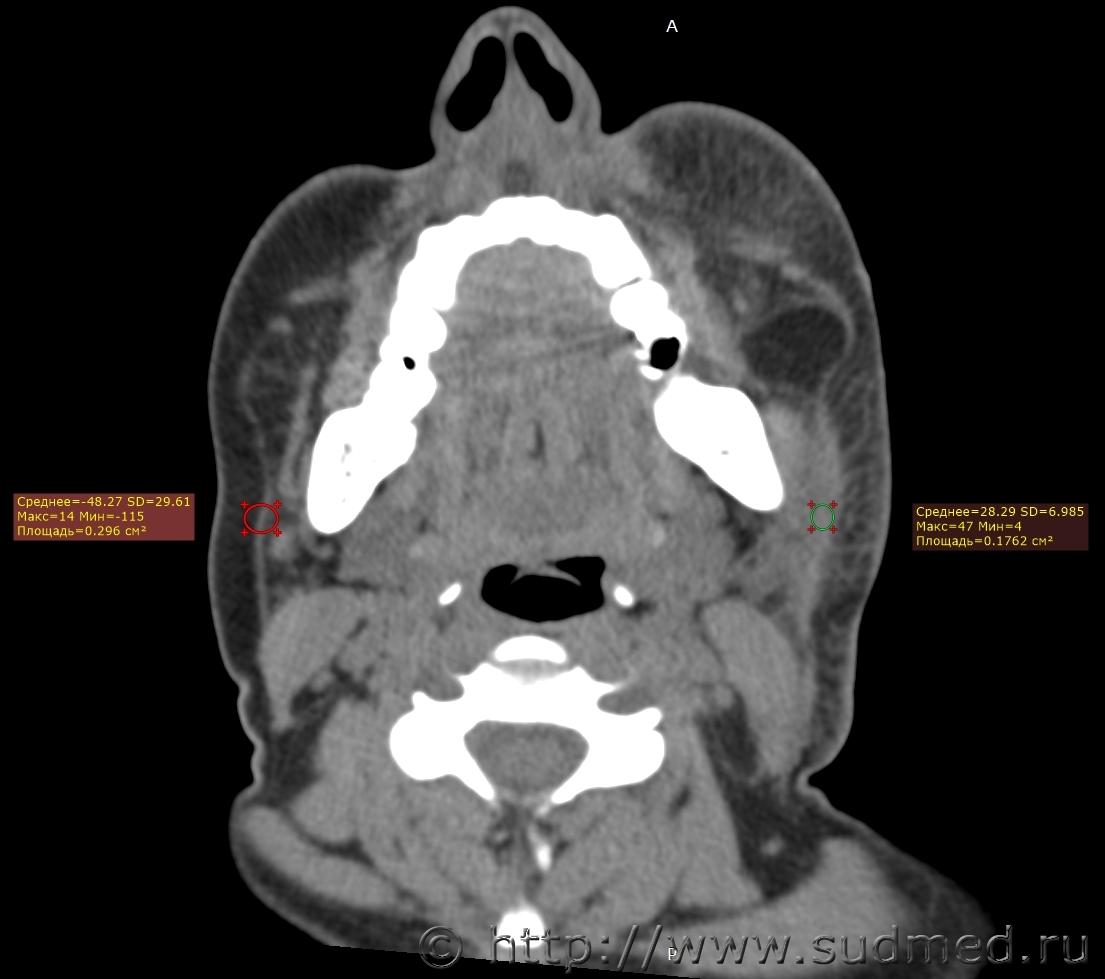

При экспертизе живого лица по медицинским документам встретились переломы шиловидных отростков височных костей. Женщина 39 лет, обратилась за медицинской помощью на 5-е сутки после травмы, тогда же провели РКТ. До этого никуда не обращалась. В протоколе РКТ отметили перелом шиловидного отростка левой височной кости, на снимках перелом на границе верхней и средней трети, дистальный отломок слегка смещен кпереди, каких-либо признаков заживления нет. Длина отростка 2,19 см. Судебная медицина - Прикрепленное изображение Также на КТ визуализируется перелом шиловидного отростка правой височной кости в нижней трети с выраженным смещением, думаю, отрывного характера (его длина 2,01 см), также без каких-либо признаков заживления Судебная медицина - Прикрепленное изображение; и гематома теменной области слева с переходом, в частности, на левую височную область, область левого сосцевидного отростка, левые околоушно-жевательную и скуловую области, левую боковую поверхность шеи Судебная медицина - Прикрепленное изображение, увеличение в объеме, нечеткость контура и разволокнение левой грудино-ключично-сосцевидной мышцы и левой ременной мышцы головы в верхней трети Судебная медицина - Прикрепленное изображение, вокруг них, в том числе кнутри от ременной мышцы, повышение плотности ПЖК Судебная медицина - Прикрепленное изображение; такие же изменения плюс повышение плотности левой подкожной мышцы шеи Судебная медицина - Прикрепленное изображение, увеличение в объеме и нечеткость контура левой околоушной слюнной железы, левая жевательная мышца не изменена Судебная медицина - Прикрепленное изображение. У подъязычной кости вижу нарушения целостности левого большого рога, но окостенение не завершено, края четко не визуализируются, поэтому о характере нарушений целостности не могу судить. Судебная медицина - Прикрепленное изображение Судебная медицина - Прикрепленное изображение В осмотрах врачей какие-либо изменения в области шеи, изменения голоса, соответствующие жалобы не отмечены; на 6-е сутки выставили острый фарингит. Помимо этой травмы есть переломы костей носа, там ничего особенного.

Изменения левой подкожной мышцы шеи наводили на мысль об удушении, но так как эта мышца без фасции, возможно, эти изменения за счёт натека. Пока не решила, выносить их в травму или нет.